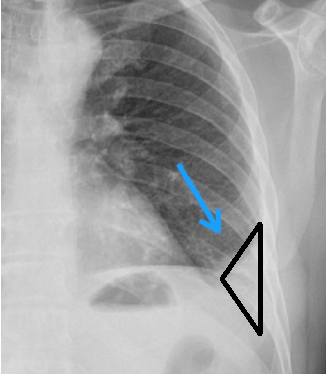

Qual alteração radiológica é possível ser vista neste RX de tórax?

É sinal sugestivo de quê?